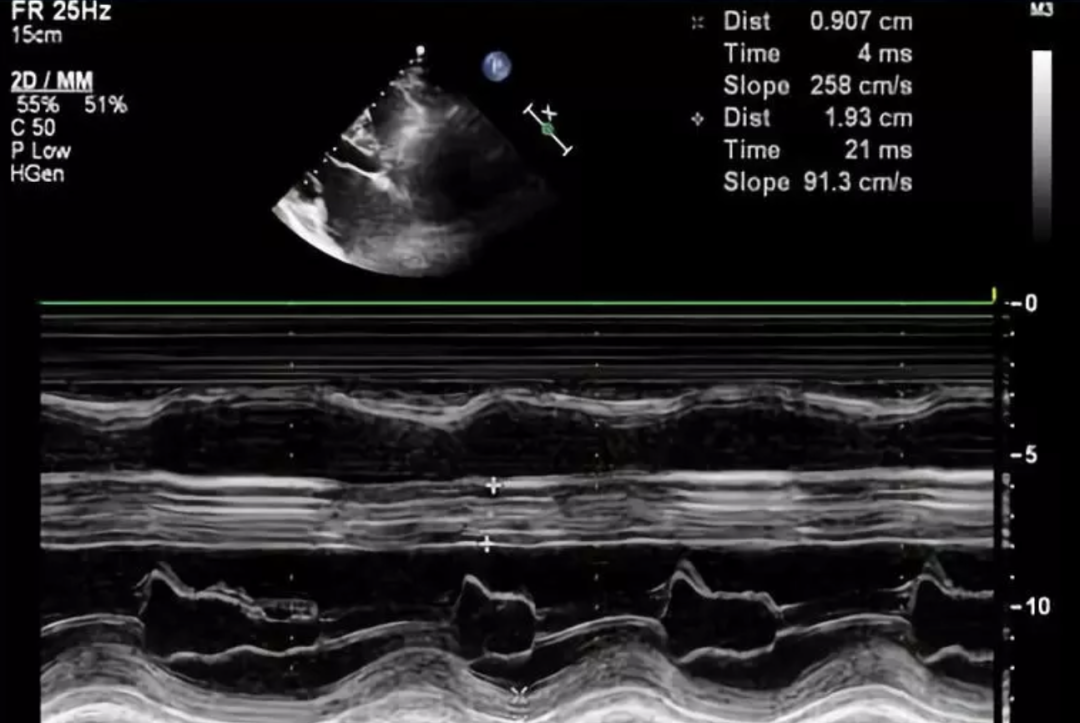

图13-28 m型超声sam征(箭头)2.

2·m型超声心动图 (1)梗阻者二尖瓣c‐d段呈多层弓背样隆起,称为sam